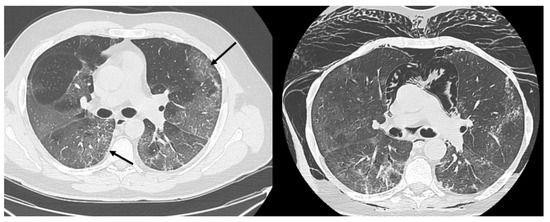

HRCT of the chest showed diffuse bilateral ground glass opacities (GGO) in all patients (Figure 1). Reticulation (Figure 2), traction bronchiectasis/bronchiolectasis (Figure 3), crazy paving and distortion (Figure 4) were observed in 29 patients (64%) at baseline. The total severity score was significantly higher at baseline in patients who eventually developed severe versus non-severe ARDS and pneumomediastinum/pneumothorax (16 versus 14; 95% CI 0.42 to 3.88; p = 0.01), as reported in Table 1. No other significant difference was observed at baseline.

Figure 4.

Crazy paving (arrow) and loss of volume of the upper right lobe.